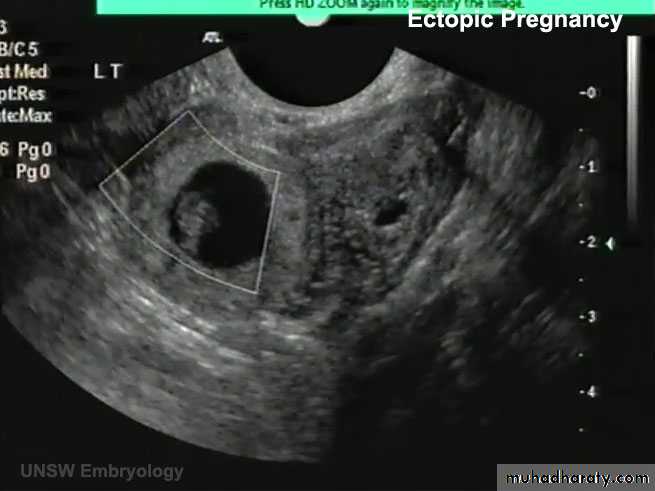

ECTOPIC PREG (EXTRAUTERINE PREG):

- 95% …. Uterine tube… and mostly in the ampula

ABNORMAL IMPLANTATION

Abnormal implantation sites of the blastocyst.

1, implantation in the abdominal cavity. The ovum most frequently implants in the rectouterine cavity (Douglas’ pouch) but may implant at any place covered by peritoneum.2, implantation in the ampullary region of the tube.

3, tubal implantation.

4, interstitial implantation, that is, in the narrow portion of the uterine tube.

5, implantation in the region of the internal os, frequently resulting in placenta previa.

6, ovarian implantation.

• A 23-year-old woman consulted her physician about severe right lower abdominal pain. She said that she had missed two menstrual periods. A diagnosis of ectopic pregnancy was made.

What techniques might be used to enable this diagnosis?

What is the most likely site of the extrauterine gestation (pregnancy)?

How do you think the physician would likely treat the condition?